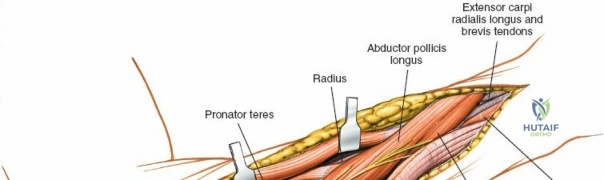

The anterior approach to the radius is an elegant example of utilizing true internervous planes to achieve deep exposure without denervating musculature. Distally, the internervous plane lies between the brachioradialis muscle (innervated by the radial nerve) and the flexor carpi radialis muscle (innervated by the median nerve). Proximally, the plane transitions to lie between the brachioradialis (radial nerve) and the pronator teres muscle (median nerve). Exploiting this plane allows the surgeon to mobilize the entire lateral muscular compartment (the "mobile wad" comprising the brachioradialis, extensor carpi radialis longus, and extensor carpi radialis brevis) away from the anterior flexor compartment.

With the forearm fully supinated, identify the broad insertion of the supinator on the anterior aspect of the radius. Incise the supinator directly along the line of its insertion onto the bone. It is critical to detach the muscle by dividing its insertion sharply at the bone, rather than splitting the muscle belly, which would risk cutting the PIN.

Proceed with strict subperiosteal dissection, elevating the supinator laterally off the bone. This is one of the rare instances in orthopedic surgery where the safety gained by staying in a subperiosteal plane completely outweighs the theoretical vascular damage to the bone caused by periosteal stripping. The elevated supinator muscle belly now acts as a protective cushion for the PIN.